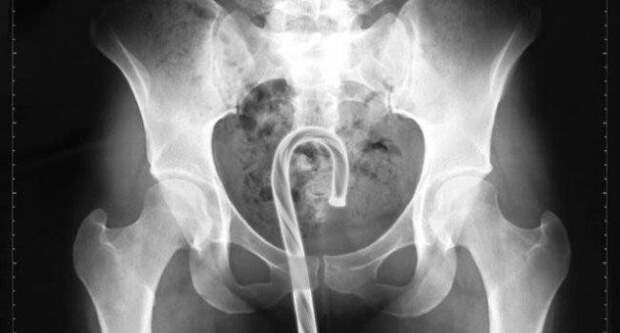

Фельдшер скорой помощи решила рассказать пользователям сети о любителях определенных экспериментов с пятой точкой и возможных последствиях для здоровья этих людей.